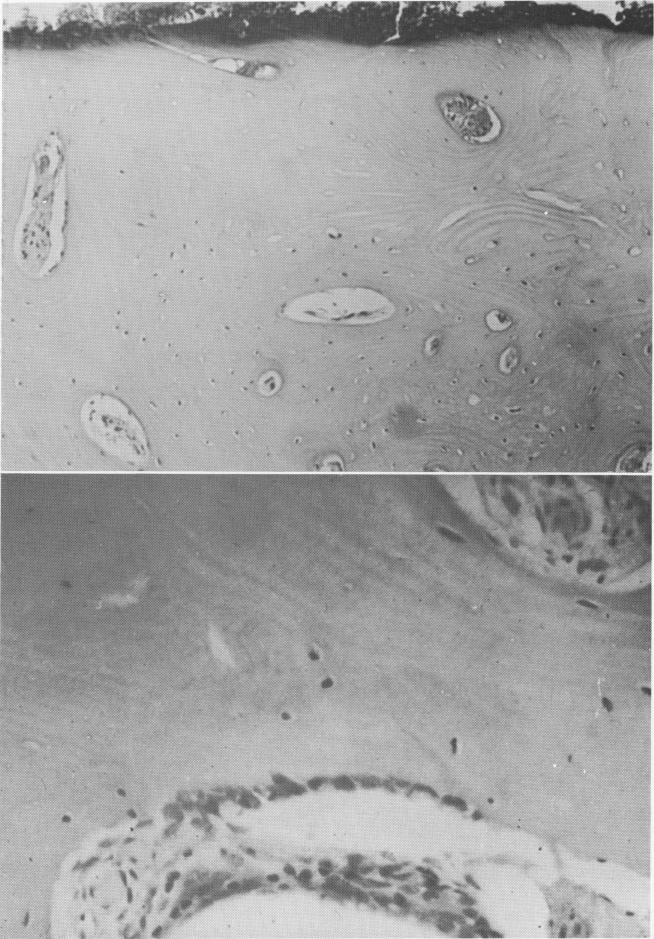

Fig. 4-59. A, Lacunae and marrow spaces containing fibrovascular tissue. The lacunae on the outer aspect of the bone are devoid of osteocytes. B, Healthy bone fragment between two large marrow spaces.

1 Outer surface of bone devoid of osteocyte at vent plant implant site

2 Proximity of vent plant implant to inferior alveolar canal in mandible